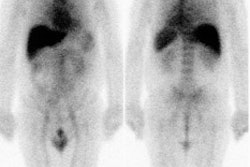

Hyperinsulinemia: The patient below had

a normal glucose level and was injected for an FDG PET

scan. Imaging revealed intense cardiac uptake and a large

about of muscular activity. The findings are consistent

with a hyperinsulinemic state and the patient subsequently

admitted to eating a small breakfast. |